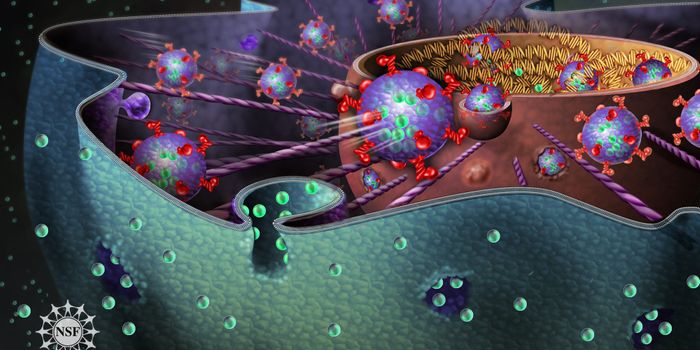

JUL 05, 2020Cell & Molecular BiologyThe pandemic virus SARS-CoV-2 enters the body through the respiratory system to cause the illness COVID-19. But we know ...